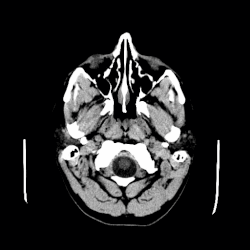

A CT scan of an arachnoid cyst